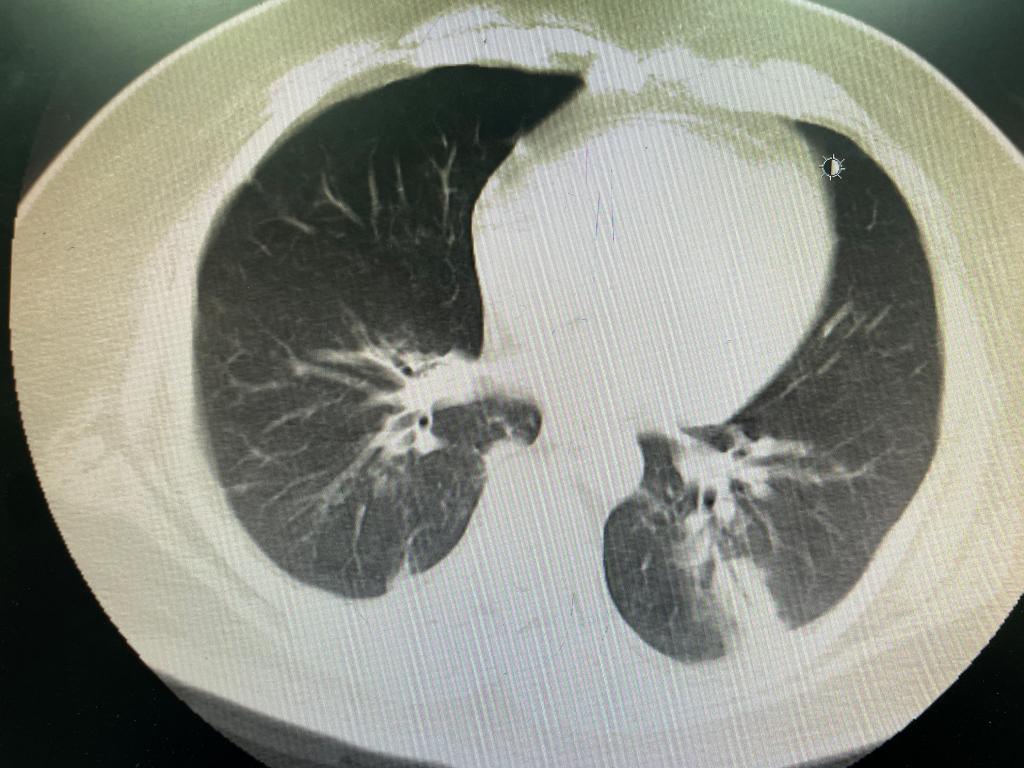

图5 ECMO下机后复查CT